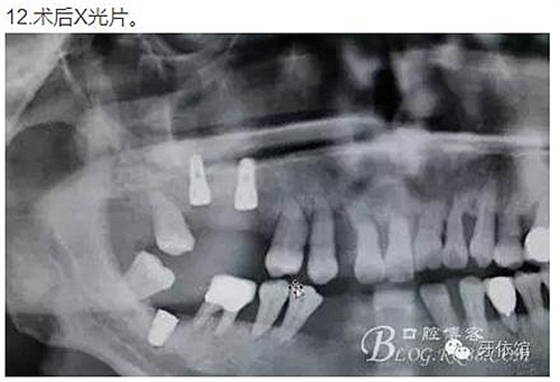

患者女,52歲,全口牙周病,不久前本院大夫剛剛為其做牙周潔治,但余留牙骨喪失嚴(yán)重,穩(wěn)定性差,不知是大夫口才好,還是患者覺悟性高,這種條件也要求種牙。